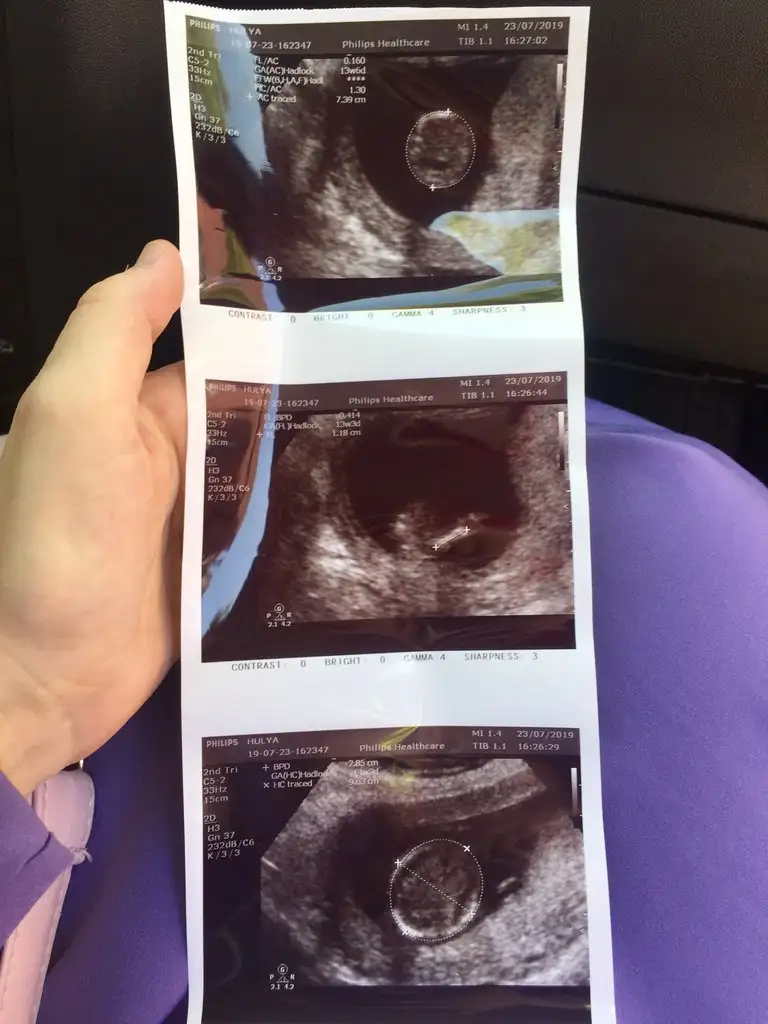

Yaptı net değil 1 ay sonra dedi erkeğe benziyo dedi geçen sene kızımda Dr yüzde doksan erkek demişti sonra kızım olacağını öğrenmiştim ama kucağıma almak nasip olmadı15 haftadasınız dr yorum yapmadımı 11 yada 12 hafta olmalı nub için

rica etsem Bakabilir msiniz nuba göre :))Eki Görüntüle 2290731 Eki Görüntüle 2290732

Bebeğin arkası mı bu ?Canım hala kız gibi.doktor söylemedi mi

Amin inşallah. Evet şimdi daha büyük olduğu ve Dr kesin bir şey demediği yeni görüntüleri olduğu için sordumSaglıkla gelsin bebeginiz inşallah daha önce sanki size tahminde bulunmuştum 11-12 haftalık usg nize erkek tahmini etmiştim nub teorisinde dimi

Ben sırt üstü yatar şeklinde görüyorum canım.nuhu göremedim bu usg de.muhtemelen nub falan kalmamıştır artık.kafa yapısı kız bebişBebeğin arkası mı bu ?

Ben kıza benzettimBenimki nedir kızlar bır bakın catlıcam öeraktan

Bebeğim erkekmişBen sırt üstü yatar şeklinde görüyorum canım.nuhu göremedim bu usg de.muhtemelen nub falan kalmamıştır artık.kafa yapısı kız bebiş

Amin İnşAllah %99 erkek dedi emin cnmO kadar emin kız demişim ki sana cok sasırdım hayırlı Canım sağlıkla gelsin inşallah emin mi doktor